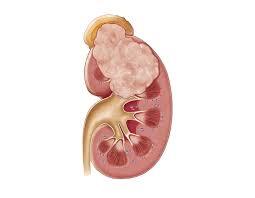

Wilms tumor is a rare form of kidney cancer that primarily affects children, most commonly under the age of five. It develops when immature kidney cells grow abnormally and form a tumor in one or both kidneys. Although the condition can sound alarming, advancements in pediatric oncology have made Wilms tumor one of the most treatable childhood cancers when detected early.

Diagnosing Wilms tumor involves a detailed medical assessment and specialized imaging tests. These investigations help doctors determine the size, location, and stage of the tumor.

Early diagnosis allows doctors to develop a precise and effective treatment plan.

How is Wilms tumor diagnosed?

Doctors diagnose Wilms tumor through physical examinations, imaging tests such as ultrasound or CT scans, and sometimes a biopsy.